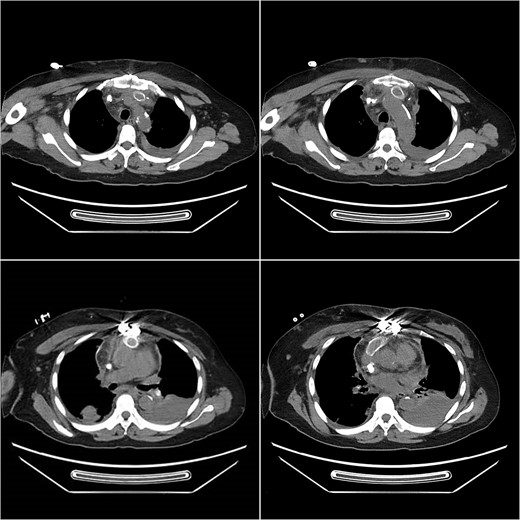

After a cardiac surgery consultation, the innominate-to-right-atrial bypass grafting technique under extracorporeal circulation and right atrial thrombus removal was planned. After anesthesia induction, the patient underwent central venous catheter placement in the left femoral vein as a route for anesthetic and vasoactive drugs. After the patient was fully heparinized, the sternum was opened for aortic cannulation and inferior vena cava drainage to establish extracorporeal circulation. During the operation, the right atrium was opened and a large calcified thrombus attached to the tunneled cuffed catheter was removed. Subsequently, the narrowed part of the unnamed vein was excised, and an artificial blood vessel (Gore R14030030L14mm*30 cm*30 cm) was anastomosed to the proximal end. After excising part of the right atrial appendage, the distal end of the artificial blood vessel was anastomosed to it, forming an innominate vein-to-right atrium artificial blood circulation (Fig. 1). The tracheal catheter was successfully removed after the operation. The patient currently has no symptoms such as arm swelling. The artificial blood vessel is unobstructed (Fig. 2), and normal dialysis is performed using the tunneled cuffed catheter.

Postoperative computed tomography angiography (CTA) showed no contrast agent leakage in the artificial blood vessel.